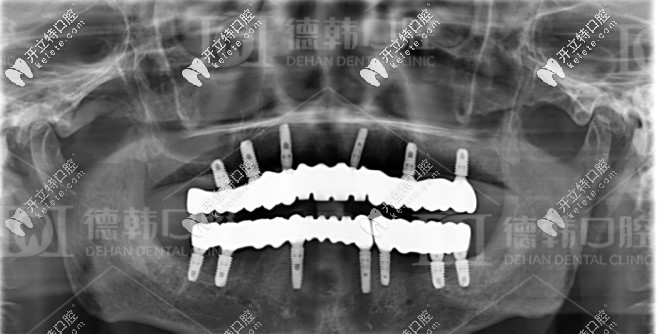

種牙成功后的牙片

張?jiān)洪L(zhǎng)針對(duì)爺爺年齡大、口腔條件不佳的情況,為其制定了一套即拔即種的全口種植方案:總共種植了13顆種植體,其中下頜種植7顆種植體,十五天后再種植上半口,上頜種植了6顆種植體。

經(jīng)過種植體埋入、放置基臺(tái)及裝牙冠等流程,一共花費(fèi)了6個(gè)月,爺爺終于恢復(fù)了滿口牙。